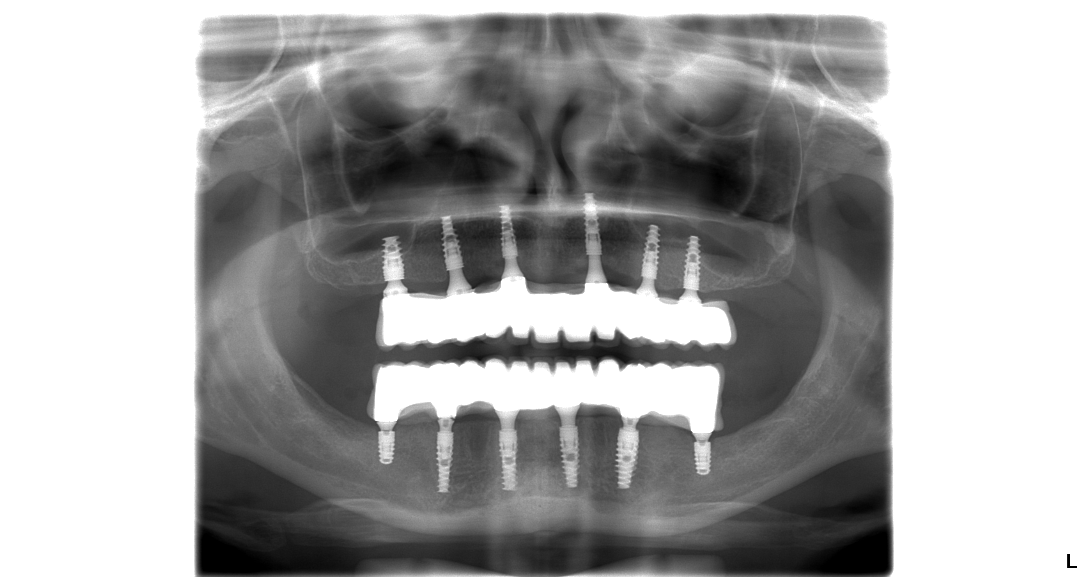

Hneď po implantácii sa pacientovi nasádza na zavedené implantáty dočasný zubný mostík, ktorý sa fixne pripevní k implantátom. Dočasný zubný mostík je spevnený titánovou konštrukciou pre maximálnu trvácnosť a stabilitu.

Približne po 10 dňoch po zákroku sa pacient vráti na kliniku na kontrolu hojenia zubného implantátu a odstránenie stehov. Integrácia zubného implantátu do kosti trvá približne 2 – 3 mesiace.

Posledný krok – nasadenie keramického mostíka

Po úspešnom zahojení zubných implantátov a vyrobení trvalého zubného mostíka nasleduje nasadenie fixne na zubné implantáty. Je to posledný krok k dokonalému úsmevu vďaka ktorému bude váš život plnohodnotnejší.

Pacientka Eva podstúpila implantáciu hornej a aj spodnej čeľuste v celkovej narkóze. Vo vrchnej čeľusti pacientka nosila snímateľnú protézu, ktorá vzhľadom na jej vek nebola dobrým riešením. Preto sa rozhodla pre radikálnu zmenu. A ako napísala v dotazníku po ošetrení bola veľmi spokojná s finálnym výsledkom.